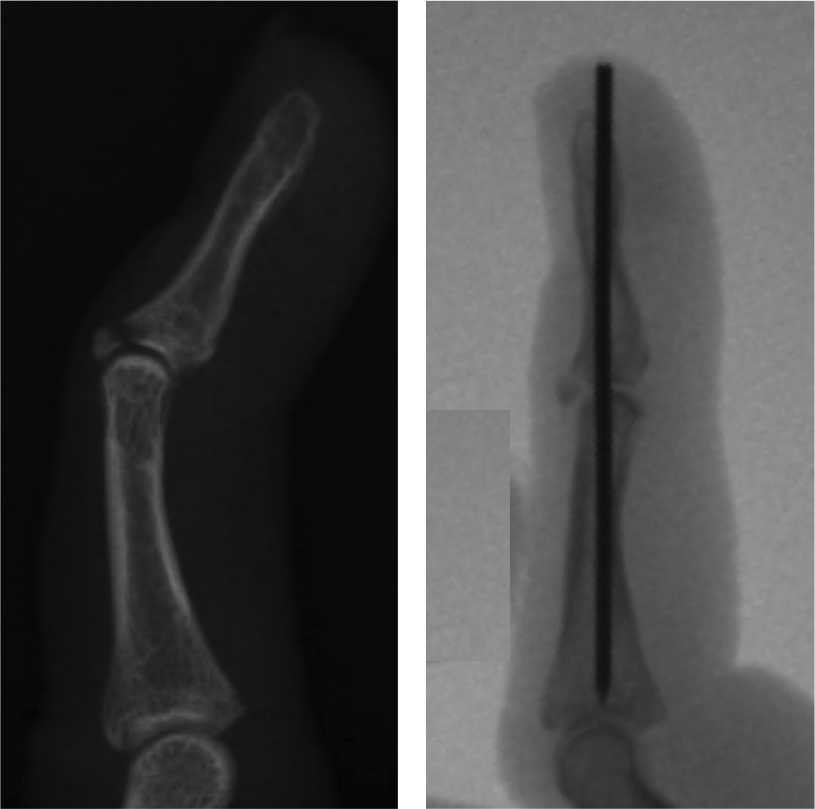

Mallet Finger Before And After. mallet finger is an injury to the tendon that straightens the tip of your finger or thumb. It's a common sports injury and is treated using a splint. mallet finger is an injury to the tendon at the tip of your finger that prevents you from straightening it. It is often caused by catching the finger “end. mallet finger is an injury to the end of the finger, causing the tip to bend. Learn how to treat it with splinting, surgery, or exercises, and see before and after photos of mallet finger recovery. learn about mallet finger, a deformity of the finger caused by injury to the extensor tendon or bone. mallet finger is a deformity of the finger caused by a damaged extensor tendon that prevents the fingertip from. Find out how long you. a mallet finger injury is a tear of tendon that straightens the end joint of the finger. learn how to treat mallet finger, a condition where the tip of your finger bends down and does not straighten. See examples of mallet finger before and after.

Learn how to treat it with splinting, surgery, or exercises, and see before and after photos of mallet finger recovery. mallet finger is an injury to the end of the finger, causing the tip to bend. See examples of mallet finger before and after. learn about mallet finger, a deformity of the finger caused by injury to the extensor tendon or bone. It's a common sports injury and is treated using a splint. mallet finger is an injury to the tendon that straightens the tip of your finger or thumb. learn how to treat mallet finger, a condition where the tip of your finger bends down and does not straighten. It is often caused by catching the finger “end. a mallet finger injury is a tear of tendon that straightens the end joint of the finger. Find out how long you.